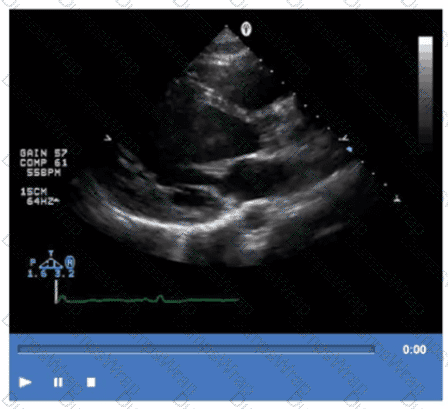

Which step is next in further evaluation of the abnormality shown in this video?

CExplanation:

Comprehensive and Detailed Explanation From Exact Extract:

The video suggests an atrial septal abnormality possibly a patent foramen ovale or interatrial shunt. To evaluate for right-to-left shunting across an atrial septal defect, the administration of agitated saline contrast with a Valsalva maneuver is the next best step.

Valsalva increases right atrial pressure transiently, promoting transient right-to-left shunting, making microbubbles visible in the left atrium if a shunt is present. Administration without Valsalva reduces sensitivity. The choice of arm vein (right or left) is less critical.

This diagnostic technique is well described in ASE adult congenital heart disease guidelines and echocardiography contrast protocols【12:ASE Contrast Echocardiography Guidelines†p.190-195】【16:Textbook of Clinical Echocardiography, 6e†p.575-580】.